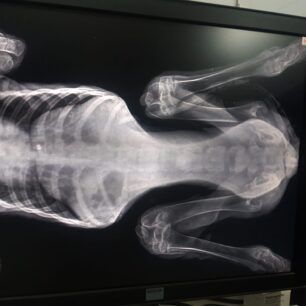

Έκκληση για να καλυφθούν τα έξοδα περίθαλψης ενός κουταβιού που βρέθηκε παράλυτο στα πίσω πόδια έξω από τη Φλώρινα πάνω στις ράγες του τρένου απευθύνει  μέσω facebook η Ναταλία Σαχινίδου. Το ζώο όπως έδειξαν οι ακτινογραφίες έχει πυροβοληθεί με αεροβόλο.

Στις ακτινογραφίες που διενεργήθηκαν ανευρέθηκε βλήμα αεροβόλου όπλου στη θωρακική κοιλότητα οπισθοστερνικά, έντονα ελαττωμένη οστική πυκνότητα ιδιαίτερα στα οπίσθια άκρα, αξιοσημείωτη χαλαρότητα αμφοτερόπλευρα και στα δύο γόνατα πού συνάδει με εικόνα ρήξεως πρόσθιου χιαστού. Στην ουσία όπως θα δείτε και στις ακτίνες μετά από ένα σημείο το στο σχεδόν παύει να υπάρχει, αν όχι από όταν γεννήθηκε τότε στην πορεία το ζώο όσο πιο ατρωφικο γινόταν το οστό τόσο τον οδηγούσε στην κατάσταση που είναι τώρα. Ο Αslan έχει 10% πιθανότητες όχι να περπατήσει αλλά να σταθεί, παρόλα αυτά δεν θα τα παρατήσουμε αφού έχει μια ζωντάνια και μια θέληση για ζωή που θαυμάζω μετά όλο αυτό που του συνέβη στους 5 μήνες της ζωής του ... Θα ακολουθήσουμε φαρμακευτική αγωγή για την θρέψη των οστών και σε 1 μήνα θα πρέπει να πάμε ξανά να δούμε πως πάμε! Για όποιον θέλει να βοηθήσει αυτοί είναι οι λογαριασμοί του κτηνιάτρου κ Νίκου πατσινακιδη.